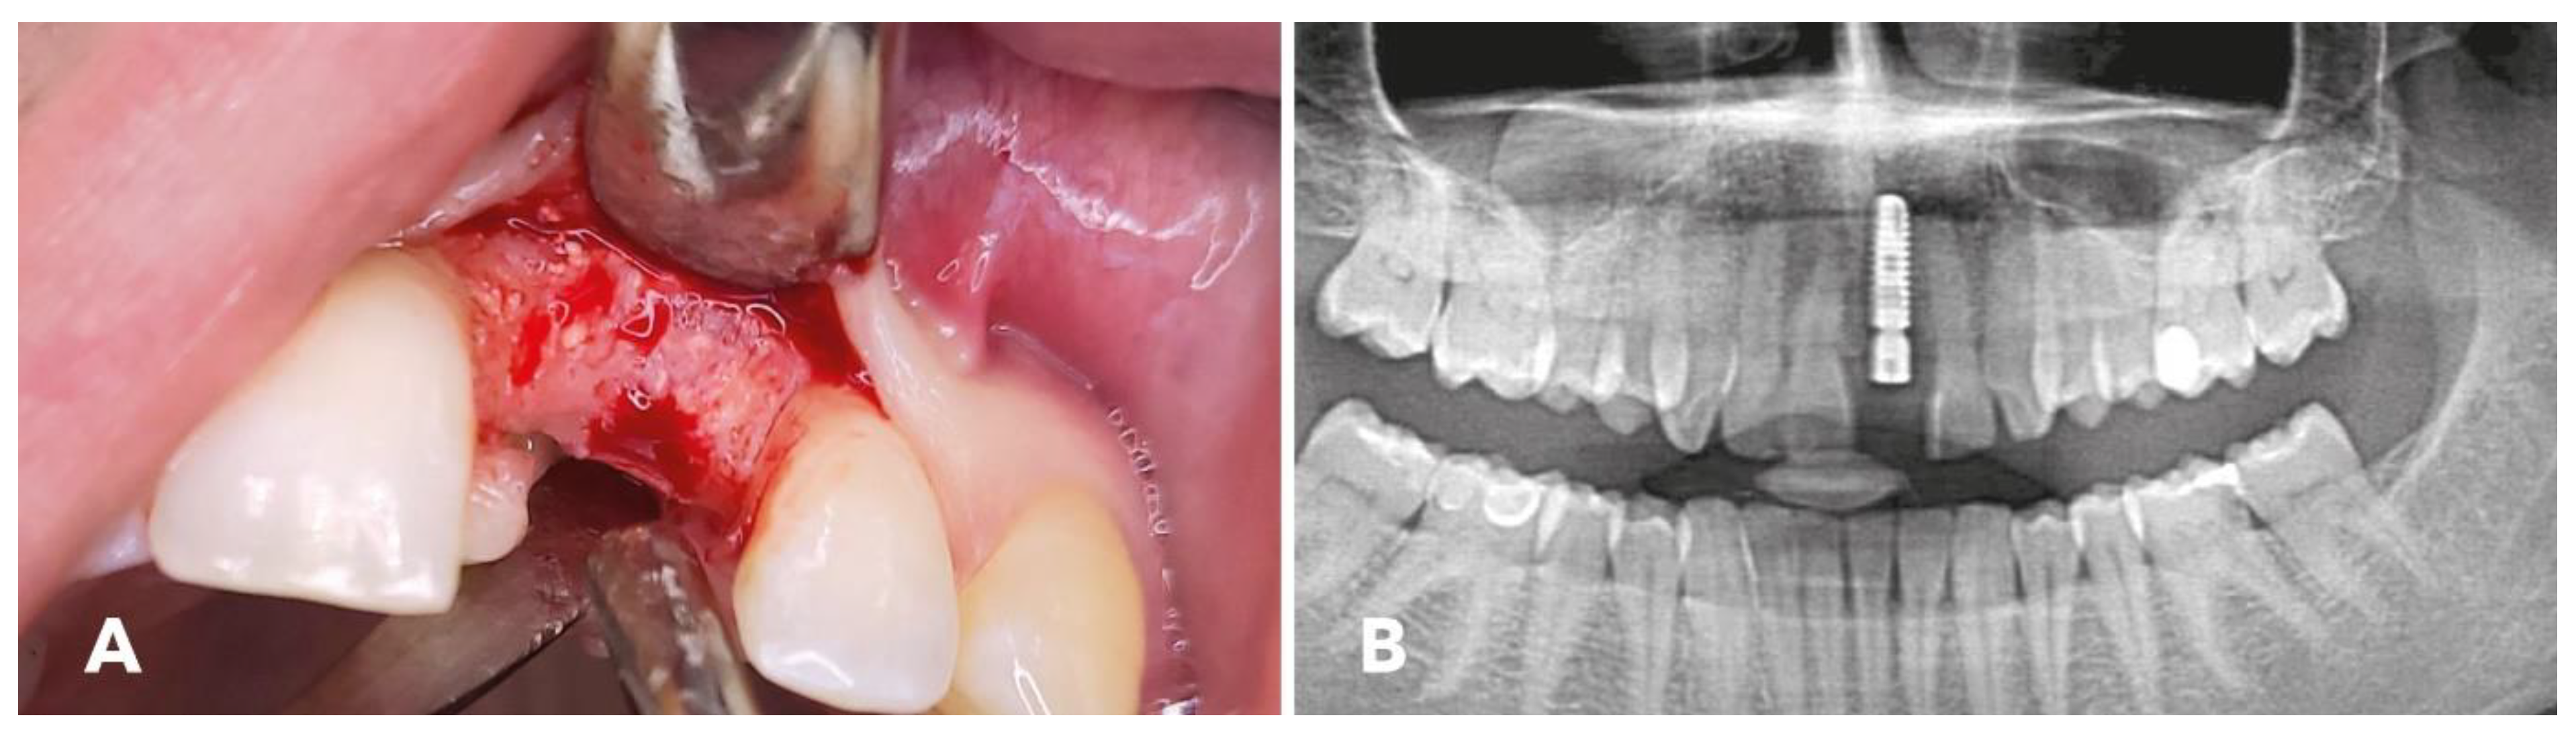

2.4. Surgical Procedure

2.5. Implantation